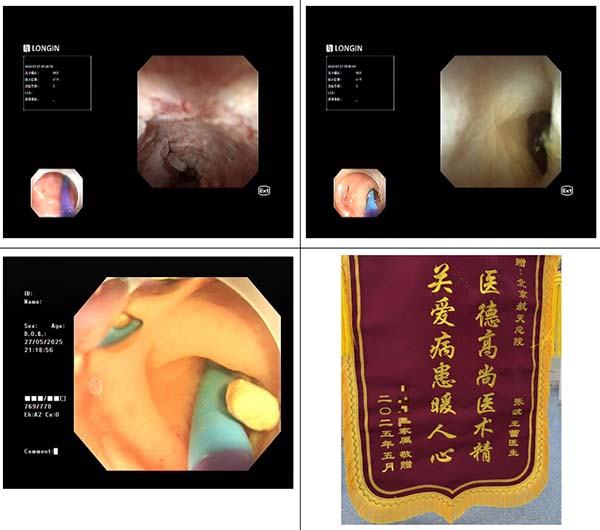

03 病例3

一(yi)名(míng)16歲高(gao)一(yi)男生(sheng),右下腹疼痛、髮(fa)熱,在(zai)北京市(shi)某三甲醫(yī)院行腹部(bu)CT提示急性闌尾炎、闌尾糞石,患者血象高(gao)、腹痛劇烈,傢(jia)屬考慮到(dao)孩子(zi)還在(zai)上學(xué),不想外科(ke)手術(shù)切除闌尾。通(tong)過(guo)我(wo)院消化內(nei)科(ke)王蕾醫(yī)生(sheng)處了(le)解到(dao),我(wo)院消化內(nei)鏡團(tuán)隊(duì)可(kě)在(zai)無射線(xiàn)條件下開展(zhan)EDAT(內(nei)鏡直視下闌尾炎治療術(shù))取出闌尾結石,閱讀外院CT影像資(zi)料後(hou),王蕾主(zhu)治醫(yī)生(sheng)立即安(an)排(pai)患者入院腸道準備(bei),次日(ri),麻醉科(ke)在(zai)人(ren)員(yuan)極其緊張的(de)條件下派出張磊醫(yī)生(sheng)爲(wei)患者進(jin)行靜脈麻醉,在(zai)患者無痛狀态下由消化內(nei)科(ke)副主(zhu)任張波(bo)及(ji)其團(tuán)隊(duì)成(cheng)員(yuan)主(zhu)治醫(yī)師康奎、護士李文(wén)傑用(yong)子(zi)鏡進(jin)入闌尾腔,見到(dao)闌尾腔糞石嵌頓咊(he)大(da)量炎性滲出,取出糞石後(hou)繼續用(yong)生(sheng)理(li)鹽水沖洗,術(shù)後(hou)患者腹痛立即緩解,第二天即可(kě)出院投(tou)入到(dao)緊張的(de)學(xué)習中(zhong),随訪患者恢複良好,傢(jia)屬也(ye)送來錦旗表示誠摯的(de)感謝(xiè)。

04 病例4

端午節(jie)第一(yi)天,一(yi)名(míng)在(zai)北四環工(gong)作(zuò)的(de)閃送員(yuan)突髮(fa)腹痛,因患者居住地距離我(wo)院相對較近,患者驅車(che)前(qian)往我(wo)院消化內(nei)科(ke)們(men)診就診,我(wo)院消化內(nei)科(ke)主(zhu)任醫(yī)師趙可(kě)經(jing)過(guo)查體(ti)初步判斷(duan)爲(wei)急性闌尾炎,後(hou)腹部(bu)CT證實急性闌尾炎,闌尾糞石嵌頓,當天陳帝醫(yī)生(sheng)将患者收入院後(hou)給予抗炎、灌腸等(deng)腸道準備(bei),次日(ri)上午副主(zhu)任張波(bo)咊(he)主(zhu)治醫(yī)生(sheng)康奎、護士李文(wén)傑爲(wei)患者行EDAT治療,患者闌尾口腫脹幾乎與回盲瓣大(da)小(xiǎo)相當,闌尾開口小(xiǎo),經(jing)過(guo)不斷(duan)嘗試,子(zi)鏡終于(yu)進(jin)入闌尾腔,用(yong)生(sheng)理(li)鹽水對患者闌尾腔灌洗,術(shù)後(hou)患者腹痛消失,通(tong)過(guo)EDAT治療,急性闌尾炎患者的(de)腹痛緩解時間咊(he)病程(cheng)均明顯縮短,出院後(hou)可(kě)立即工(gong)作(zuò),作(zuò)爲(wei)閃送員(yuan)的(de)患者專(zhuan)程(cheng)到(dao)我(wo)院送來錦旗表示感謝(xiè)。